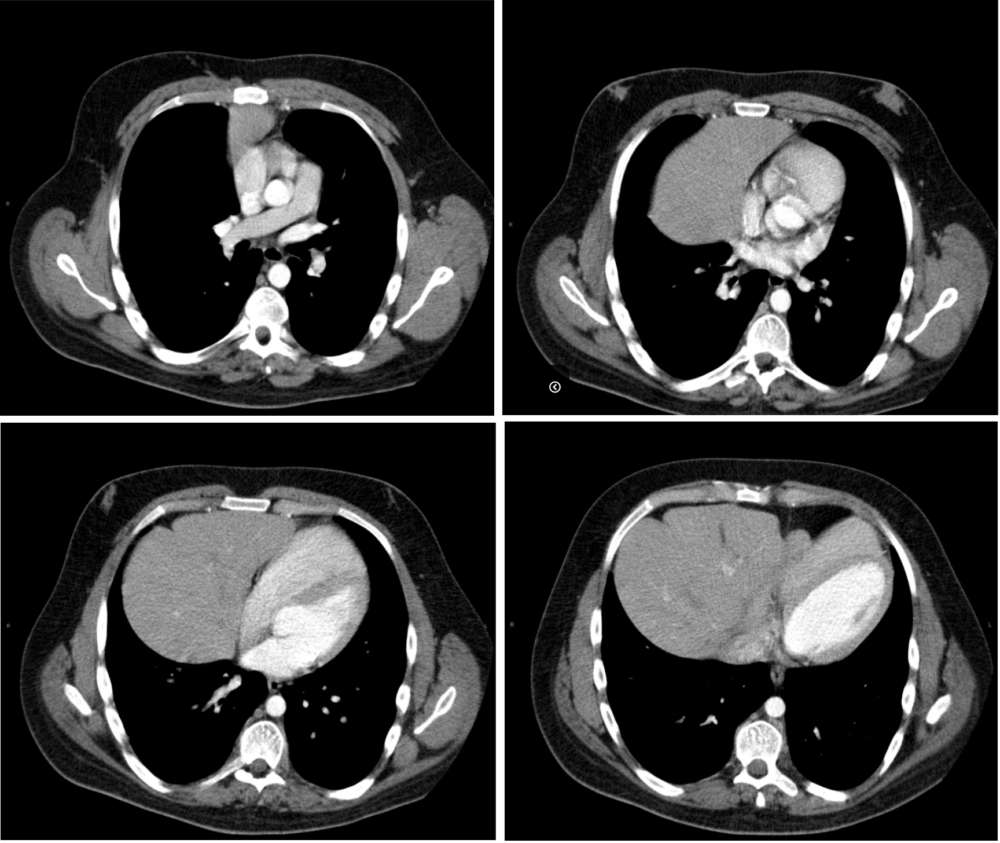

Because of his new symptoms a chest radiograph was done which unexpectedly revealed a large right paracardiac soft tissue density mass. A CT thorax was thus performed to investigate this further.

Axial CT images through lower thorax with intravenous contrast demonstrating the herniation of the left lobe of the liver together with the Gallbladder,and part of the stomach and transverse colon into the thorax via a ventral diaphragmatic defect.